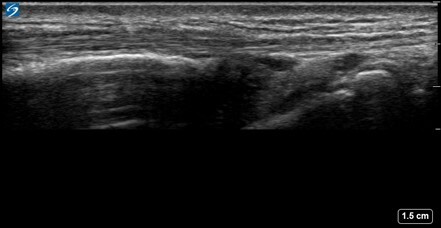

Wrist Compartment One APL Image